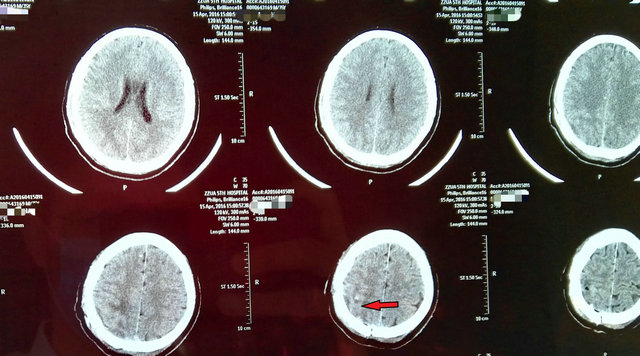

在医院的大力支持下,由神经外科一病区寿记新主任牵头组织了院内多学科会诊,决定采用超声实时引导下脑肿瘤切除的新技术。在神经外科专家以及麻醉、超声专家的共同努力下,寿记新主任亲自主刀,付旭东副主任协助,通过超声精确定位,准确的找到了肿瘤(图3),同时避开了重要的神经、血管,顺利全切病变组织(图4),术后李先生各项生命体征正常,手术获得圆满成功。术后一周,言语、偏瘫逐步恢复正常,影像复查显示肿瘤切除完整,无副损伤(图5)。

图5